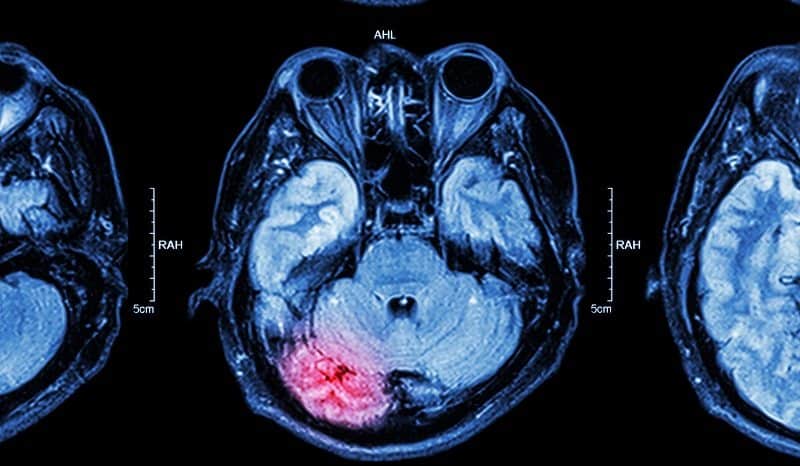

Mart, beyin yaralanmalarının nasıl meydana geldiği, beyin yaralanmalarının yaygınlığı ve beyin hasarının yaşamı değiştiren etkileri hakkında halkı bilinçlendirmek için bir fırsat olarak hizmet eden Beyin Hasarı Farkındalık Ayı'dır.

Travmatik beyin hasarı (TBI) ciddi bir sağlık sorunudur. Amerika'da herhangi bir zamanda yaklaşık 1,6 milyon insan TBI tanısı aldı veya aldı, bu da ...